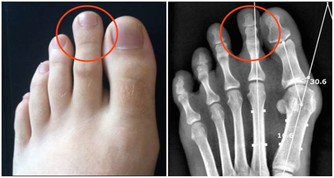

一種最簡單的方法就看看自己長的痘痘多不多。其次,結合臉色情況進行判定。一個人,如果臉上跟背部的痘痘都比較多,而且臉色暗黃,皮膚無彈性,暗淡無光,有一種營養不良的感覺,那就說明很有可能身體濕氣過重。